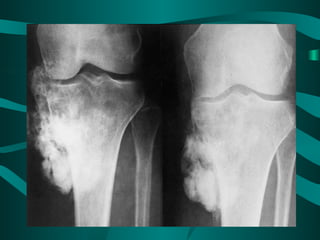

•    Classic X-ray findings:

1. Codman's triangle (periosteal elevation)

2. Sunburst pattern

3. Bone destruction

• Pathology:

– Often involves the metaphysic of long bones

– Usually around the knee (distal femur and

proximal tibia)

Classic X-ray findings: 1. Codman's triangle (periosteal elevation) 2. Sunburst pattern 3. Bone destruction